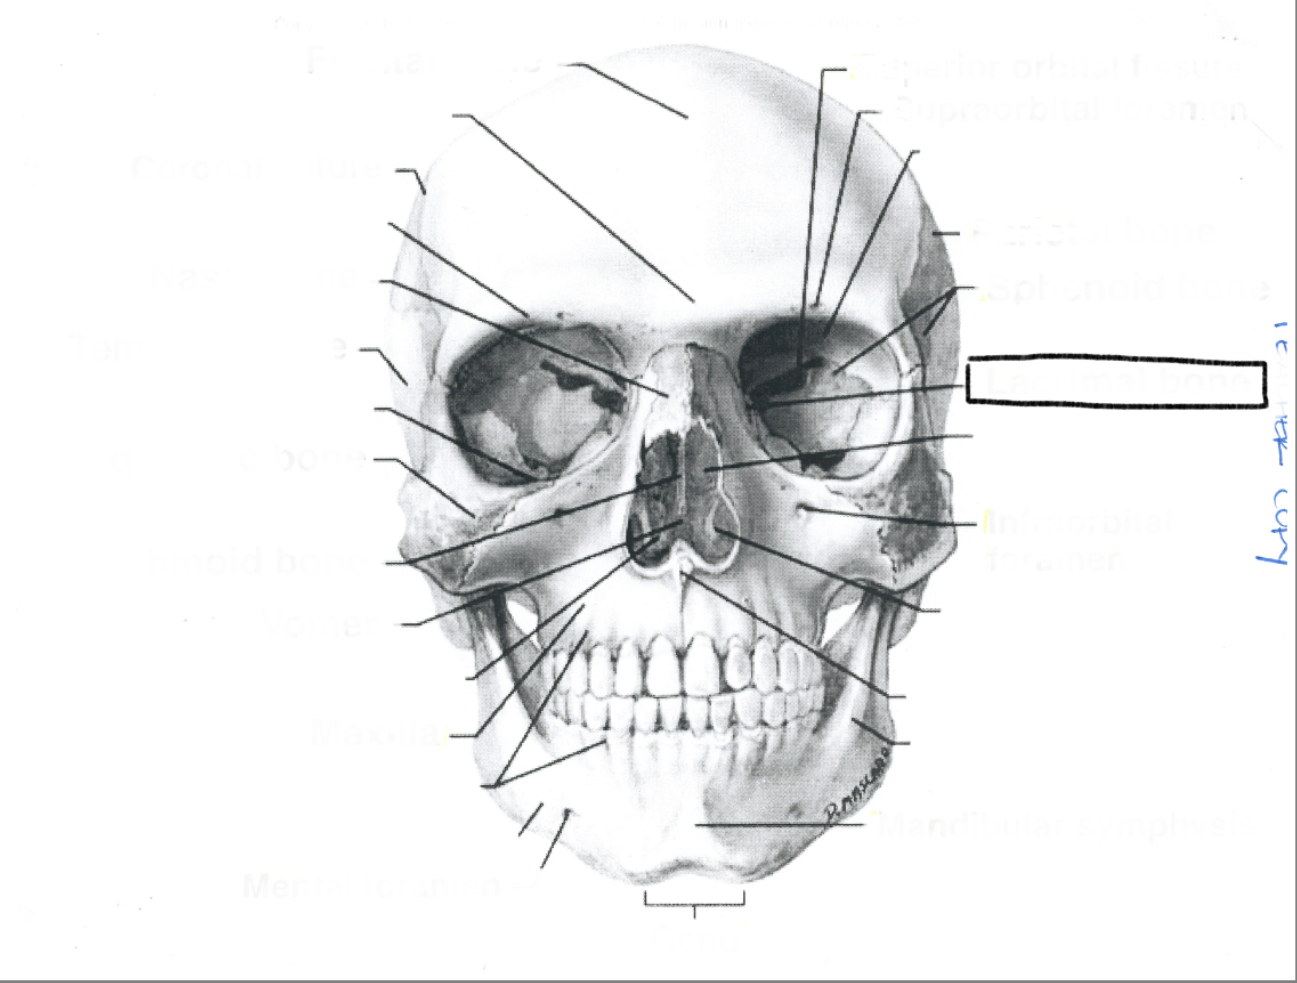

What is this?

What is this?

What is this?

What is this?

What is this?

What is this?

What is this?

What is this?

What is this?

What is this?

What is this?

What is this?

What is this?

What is this?

What is this?

What is this?

What is this?

What is this?

What is this?

What is this?

What is this?

What is this?

What is this?

What is this?

What is this?

What is this?

What is this?

What is this?